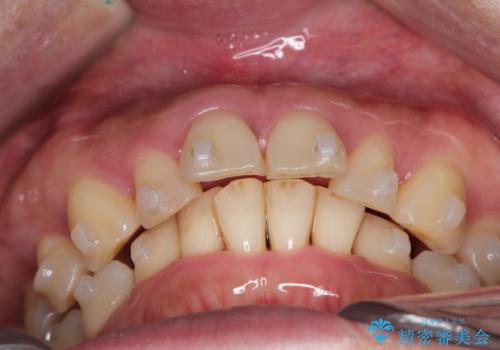

- 前歯が出ていることを主訴に来院されました。

インビザラインにて臼歯部の遠心移動及びIPRを行なっています。

叢生量が多いケースでしたが、綺麗な歯並びとなり患者様にも満足していただきました。